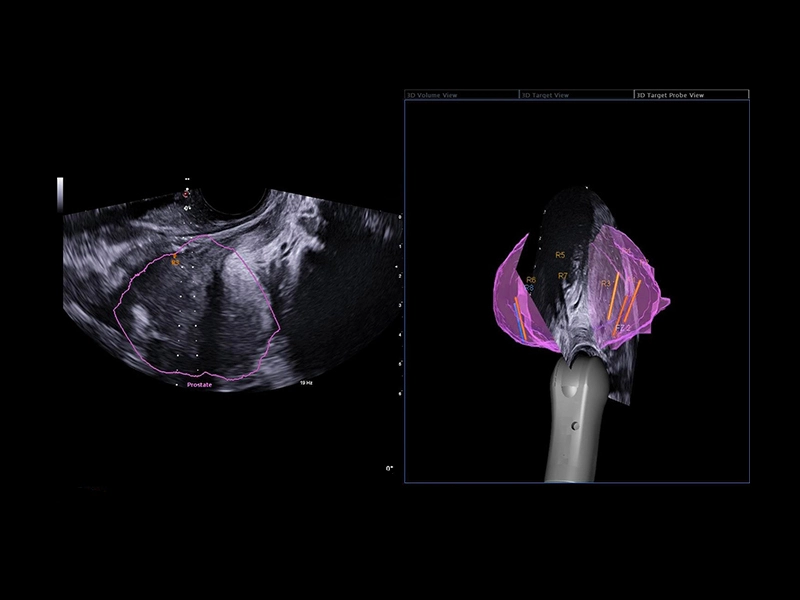

MyLab™E80 - Urofusion - TP Biopsy

MyLab™E80 - Urofusion - TP Biopsy